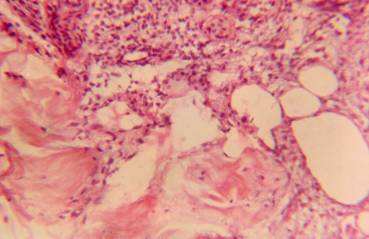

Figure

1. Presented pyonecrotic mass. Uv.h200

In

the initial period, sides and bottom of the wounds were presented

purulent-necrotic masses (Figure 1), the

thickness of which depended on the extent of tissue damage (Figure 2).

Detritus

was closely associated with developing granulation tissue.